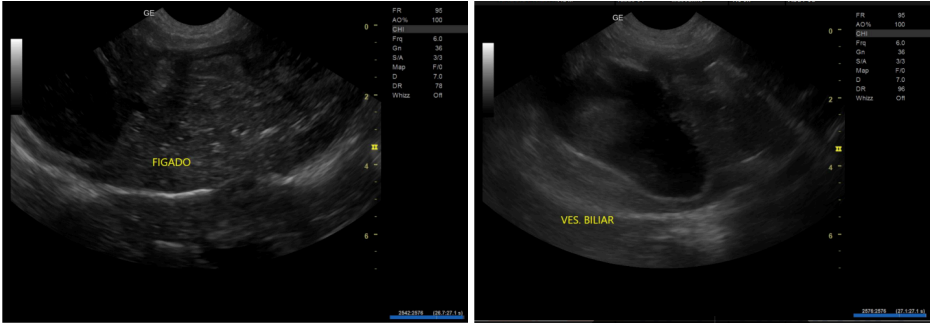

Diante do histórico e da presença de sinais neurológicos associados à alimentação, foi levantada a suspeita de desvio portossistêmico. A ultrassonografia abdominal revelou no baço alterações de ecogenicidade, padrão parenquimatoso alterado, conteúdo biliar espesso. Nos rins revelou assimetria, definição córtico-medular alterados e pielectasia. Foi evidenciado também micro-hepatia, heterogeneidade parenquimatosa e alterações vasculares compatíveis com redução do fluxo portal hepático, além embora não tenha sido possível identificar o vaso anômalo, limitação descrita em casos de anatomia desfavorável. Assim, optou-se pela realização de tomografia computadorizada contrastada para melhor caracterização vascular.

Figura 3. – Ultrassonografia do Paciente

No diagnóstico, a sequência utilizada neste caso de avaliação clínica, exames laboratoriais, ultrassonografia abdominal e posterior tomografia computadorizada, está de acordo com recomendações amplamente estabelecidas. A ultrassonografia é reconhecida como método inicial de escolha por sua disponibilidade e custo acessível; contudo, trata-se de um exame operador-dependente, que pode falhar na identificação de shunts pequenos, tortuosos ou profundamente posicionados, especialmente na presença de microhepatia ou gás intestinal (SANTILLI et al., 2003; SANTOS et al., 2019 & POSASTIUC et al., 2022). No presente caso, tais limitações foram evidentes, já que o vaso anômalo não pôde ser completamente caracterizado na ultrassonografia.

A avaliação ultrassonográfica evidenciou fígado diminuído, hipovascularização portal, alterações esplênicas e conteúdo biliar espesso, achados que fazem sentido com a fisiopatologia da doença. A microhepatia é uma consequência direta da baixa irrigação sanguínea do fluxo portal. O fígado depende desse fluxo para crescer e funcionar. Quando o sangue desvia para a veia renal, o órgão se desenvolve de forma reduzida. A hipovascularização aparece porque os ramos da veia porta ficam menos calibrosos quando o fluxo dentro deles é insuficiente ao longo dos anos. Esses pontos são descritos em estudos de Bertolini (2019) como característicos de shunts extra-hepáticos congênitos.